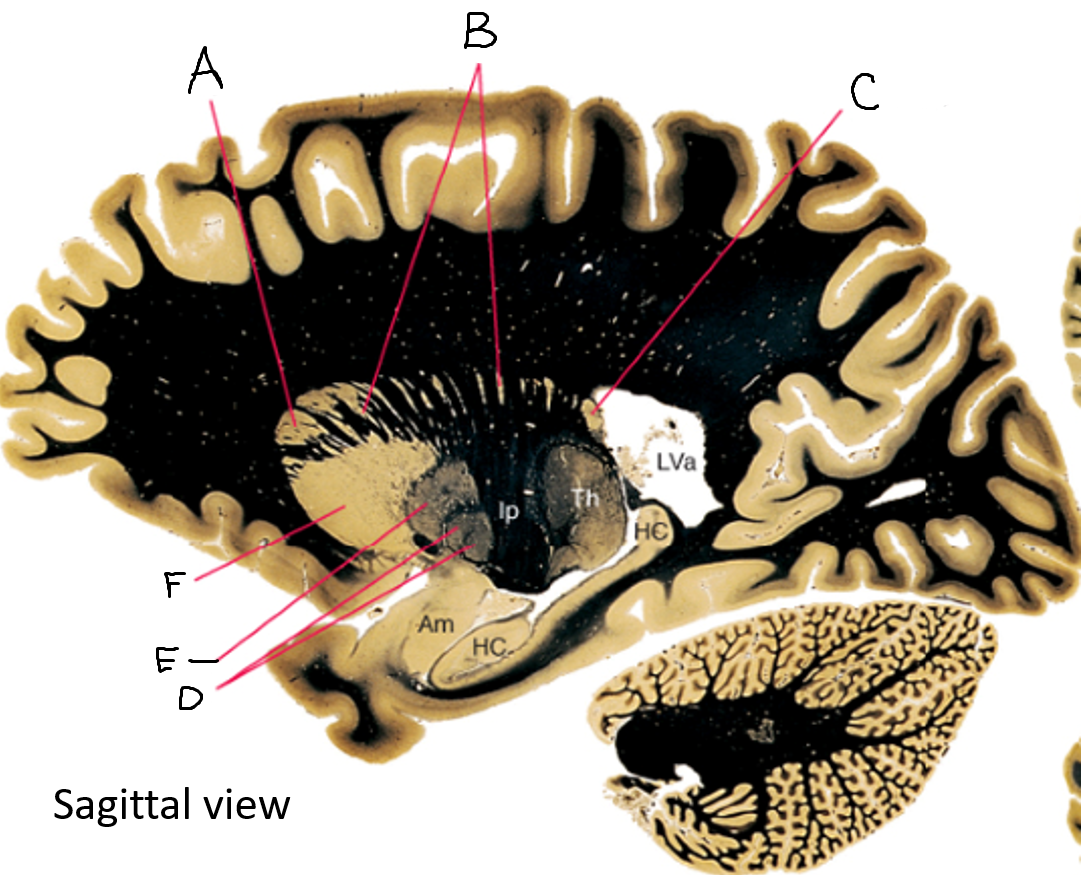

A

internal capsule (anterior limb)

B

caudate nucleus body

C

caudate nucleus head

D

putamen

E

caudate nucleus tail

F

thalamus

G

internal capsule (posterior limb)